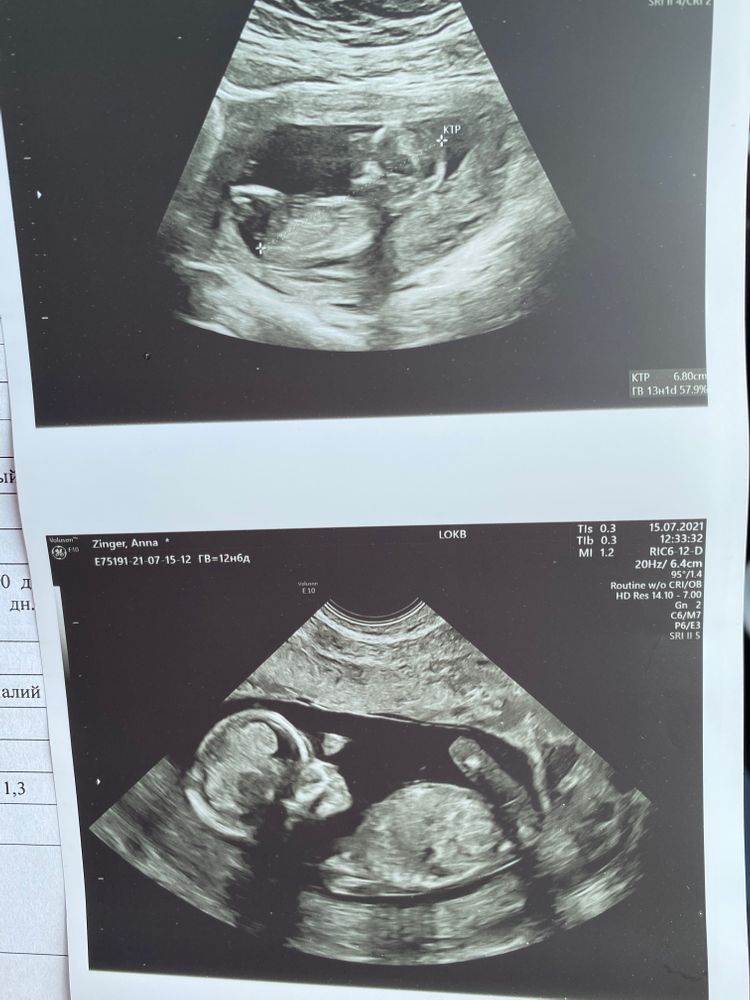

Узи 13 недель 🥰

Второе фото чётко девочка, так что я тоже за неё.

Думаю девочка. Половой бугорок на первом фото горизонтально смотрит 😁 Но только если это бугорок, а не пуповинка... поздравляю с первым скринингом!